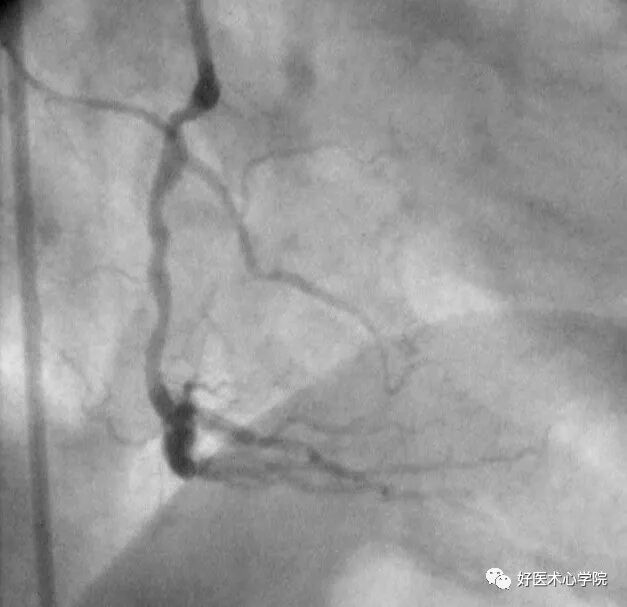

左前斜位:观察右冠全长,但难以看到远段分叉。

此时可以加足位可以观察。

造影导丝是什么珍藏 冠脉造影从流程到诊断,基础必备!_https://www.jmylbn.com_新闻资讯_第53张

△左前斜位下的右冠